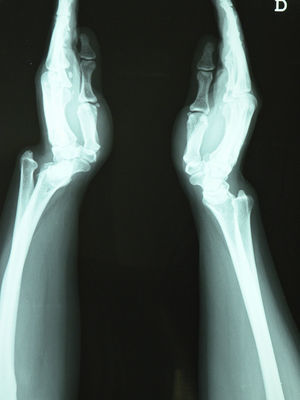

The patient is a 39-year-old woman who presented nocturnal paresthesia lasting for 6 months on both hands, but predominantly right (dominant hand). She presented mechanical pain of both wrists, with a visual analog score (VAS) of 90/100. Upon examination, there was a solid tumor on the posterior side of both wrists (Fig. 1), painful limitation of extension of the wrist and supination, mainly on the left side. The hemogram and blood chemistry were normal, as well as the neurophysiological study of the median and ulnar nerves. A karyotype demonstrated mosaicism (86% XX, 5% XXX, 9% X).

The posteroanterior wrist X-rays (Fig. 2) showed typical Madelung deformity changes on the right wrist1: shortening of the radius compared to the ulna, dorsally and radially curved radius, dorsal and radial convexity, an angle similar to the distal radial joint surface, a mismatch of the distal radioulnar joint and carpal dislocation. The lateral projection (Fig. 3) demonstrated anterior arching of the radius and dorsal dislocation on the ulnar head; the carpus was also dislocated on the ulnar side and anteriorly in the distal radioulnar joint, in a way that made the wrist bones appear to follow the arch of the radius.2 The patient was diagnosed with a carpal tunnel syndrome due to Madelung's deformity and was programmed for an evaluation by the orthopedics department but, due to a delay, medical treatment with local steroid infiltrations was carried out. 1ml of triamcinolone was injected into the right wrist using a standard technique.3 The pain improved in the next 2 days (VAS: 50/100), disappearing completely after one week (VAS: 0/100).